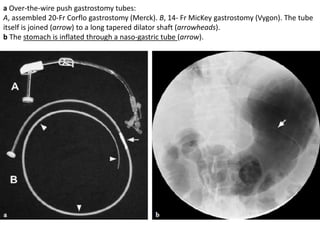

• Radiographically the tumours appear

as discrete submucosal masses

typified by a smooth mucosal surface

with borders forming right or slightly

obtuse angles to the adjacent

mucosa.

• En face, the preservation of a normal

areae gastricae pattern over the mass

confirms the presence of normal

mucosa and the extramucosal

location of tumour.

• When there is ulceration it is usually

seen as a central collection of barium

in a smooth or slightly lobulated mass.

This is sometimes called a ‘target’ or

‘bulls-eye’ lesion.

• Leiomyomas occasionally contain

coarse mottled calcifications

Leiomyoma adjacent to the gastro-oesophageal

junction shown on CT as a

smooth soft tissue mass in the contrast-filled

stomach

Leiomyoma of the stomach.

Double Contrast barium study (a) shows a well delineated smooth mass arising from the lesser

curve of the stomach.

Endoscopic-ultrasound (b) demonstrates a massive lesion which does not penetrate through the

gastric wall. Biopsy revealed a benign leiomyoma